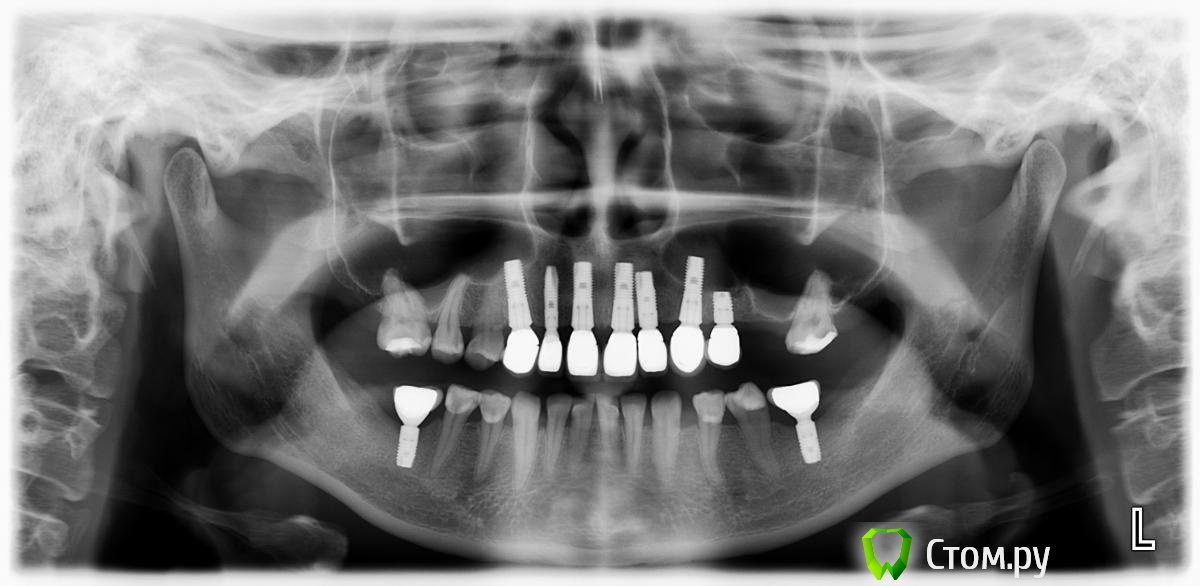

ILGAMSA Опубликовано 27 ноября, 2014 Поделиться Опубликовано 27 ноября, 2014 (изменено) это астра13, 11, 21, 23 - широкая платформа 4,512 - узкая платформа 3,0остальные - стандартная платформа 3,5/4,0отвертка обычная от любого израиля подходит.Только торки там другие. Изменено 27 ноября, 2014 пользователем ILGAMSA Ссылка на комментарий

pit Опубликовано 28 ноября, 2014 Поделиться Опубликовано 28 ноября, 2014 Я бы удалил 12,11 и 23 имплантаты (выкрутив по резьбе!!!!!), в их области поработал бы с десной и временными коронками. И сделал бы мост.Какая линия улыбки? 1 Ссылка на комментарий

zzkz Опубликовано 28 ноября, 2014 Автор Поделиться Опубликовано 28 ноября, 2014 Подскажите кто астрой торгует в Самаре и Москве астрой? Я бы удалил 12,11 и 23 имплантаты (выкрутив по резьбе!!!!!), в их области поработал бы с десной и временными коронками. И сделал бы мост.Какая линия улыбки?Линия улыбки низкая, там у нас еще ботакс присутствует, губки пухленькие.Имплантаты удаляете майзенгеровским набором? Ссылка на комментарий